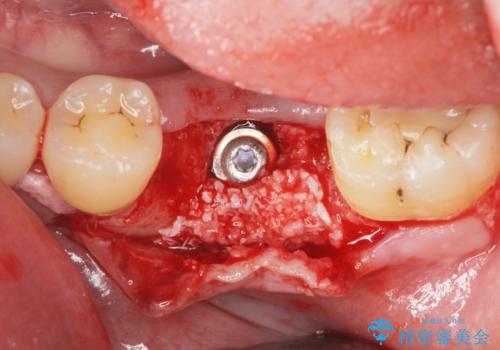

減ってしまった顎骨に増骨処置を行うことで、より安定した環境で長く使用できるようなインプラント治療を行っています。